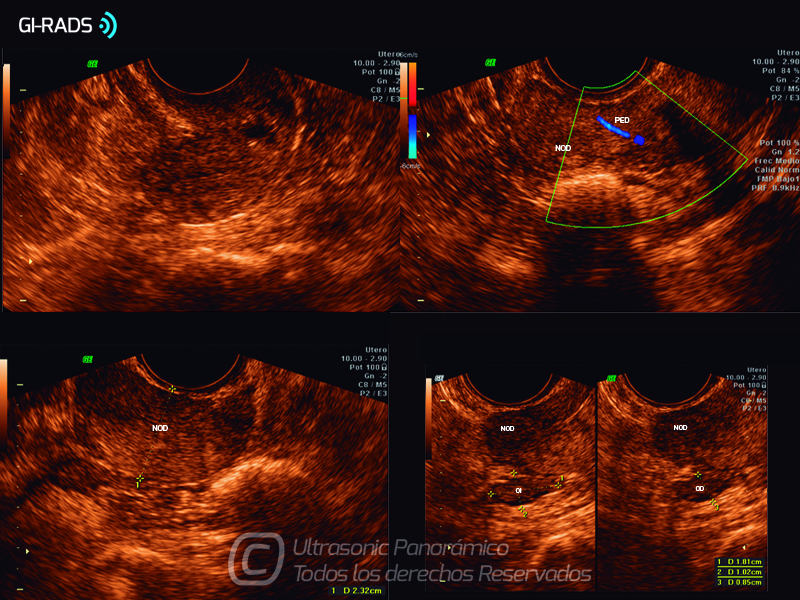

Patologías Benignas – Mioma Pediculado